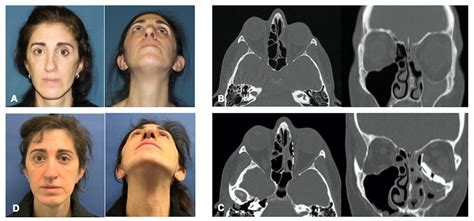

Patient Specific Implants for Orbital Reconstruction in the Treatment